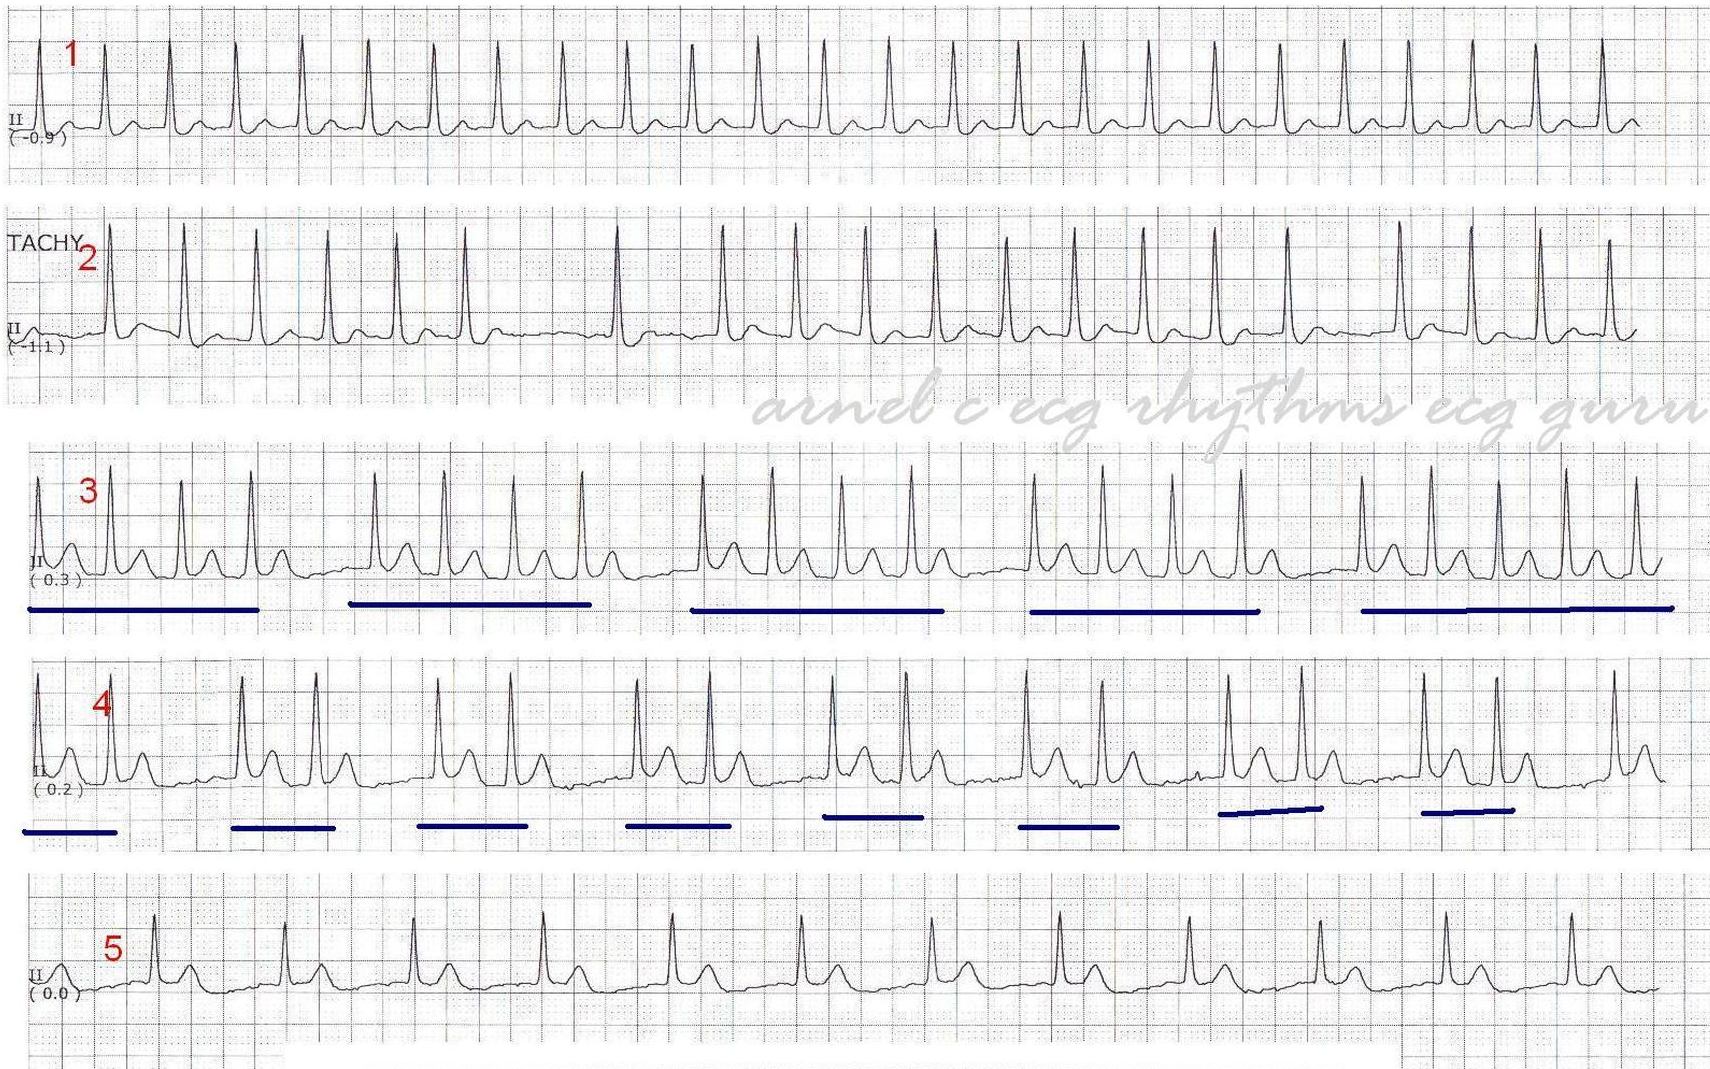

ECG Challenge: Grouped Beating - Double Tachycardia - ANSWER

This series of strips was donated by Arnel Carmona, and was taken from a patient admitted to the hospital for a urinary tract infection.  No other history is known.   On close examination of this rhythm what do we see?

Strip 1:   Narrow-complex tachycardia with NO apparent P waves.

Strip 2:   Some irregularity, with long regular groups and still NO P waves.

Strips 3 & 4:  Grouped beating.

Strip 5:   A narrow-complex rhythm that is approximately ½ the rate of Strip 1.

When grouped beating is seen, one should always suspect Wenckebach conduction.  Wenckebach conduction (progressively longer conduction times through the A-V conduction system) can occur in rhythyms other than sinus rhythm.  Without P waves and PR intervals, GROUPED BEATING is our major clue to Wenckebach conduction.

This patient has an underlying atrial fibrillation – hence no P waves.  Fine fibrillatory waves can be seen, but artifact can cause the same appearance.  So, why is there no irregular irregularity?  There is another rhythm at work here along with the atrial fibrillation.  Junctional tachycardia is seen in Strip 1.  When two tachycardias coexist, one from above the AV junction, and one from below, the rhythm can be called a “double tachycardia”.  This particular combination often happens in patients with digitalis toxicity.

In some cases, a complete heart block at the level of the atrial conduction fibers or the AV node causes  two rhythms to operate independently.  Any supraventricular rhythm, including atrial fib, can occur with a complete heart block, in which case we would see an “escape” rhythm.  Escape rhythms are usually slow, either idiojunctional (40-60 bpm) or idioventricular (< 40 bpm).

Let’s look at each of the strips in detail.  We will begin with the hypothesis that this is atrial fibrillation with concurrent junctional tachycardia at around 150 bpm.  I will include laddergrams to illustrate my view of what is happening.